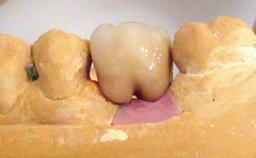

Biological complications caused by undetected cement residue have been receiving much attention. Excess cement might be responsible not only for rapidly developing of peri-implantitis, but also for delayed or chronic manifestations of the disease many years after cementation (Wilson 2009; Linkevicius and coworkers 2013). Invitro and clinical studies have shown that it is very difficult or even impossible to completely clean up excess cement at subgingival margins, so popular in cemented restorations (Agar and coworkers 1997; Linkevicius and coworkers 2011, 2012). Possible outcomes of biological complications due to excess cement range from temporary inflammation of the peri-implant soft tissues without any serious esthetic and functional consequences all the way to implant loss. This report describes a case of peri-implantitis caused by residual cement; as well as the management and quite unusual resolution of the complication. The patient presented in 2009 with a draining sinus tract, tenderness on chewing, and tissue contact above the implant-supported restoration. The implant had been restored approximately three years before.

Prosthesis Type FDP